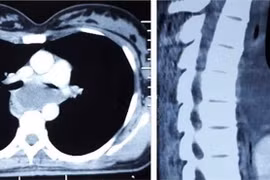

(khoahocdoisong.vn) - Trung thất được phân chia làm 3 phần: Trung thất trước, trung thất giữa và trung thất sau. Các cơ quan của trung thất có các biểu hiện bệnh tật riêng.

U trung thất trước chiếm tỷ lệ cao nhất, bao gồm u tuyến hung, u tế bào mầm… 30 – 50% các trường hợp u trung thất không có biểu hiện hoặc có một số biểu hiện không đặc trưng như: Đau ngực, khó thở, ho, sốt… Khối u vùng trung thất thường gây ra hội chứng chèn ép tĩnh mạch chủ, tim, phổi, nên rất nguy hiểm cho bệnh nhân bất cứ lúc nào. Với kỹ thuật mổ nội soi tại Bệnh viện Phổi T.Ư đã mang lại thành công và may mắn cho nhiều bệnh nhân.